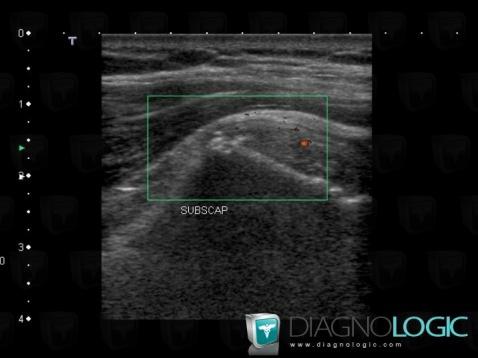

Tendinopathy / Shoulder, Sub scapularis tendon, US

Here is the specific information in the key image above:

- Diagnosis Rotator cuff tendinopathy / Shoulder, Location(s) Sub scapularis tendon, with gamuts